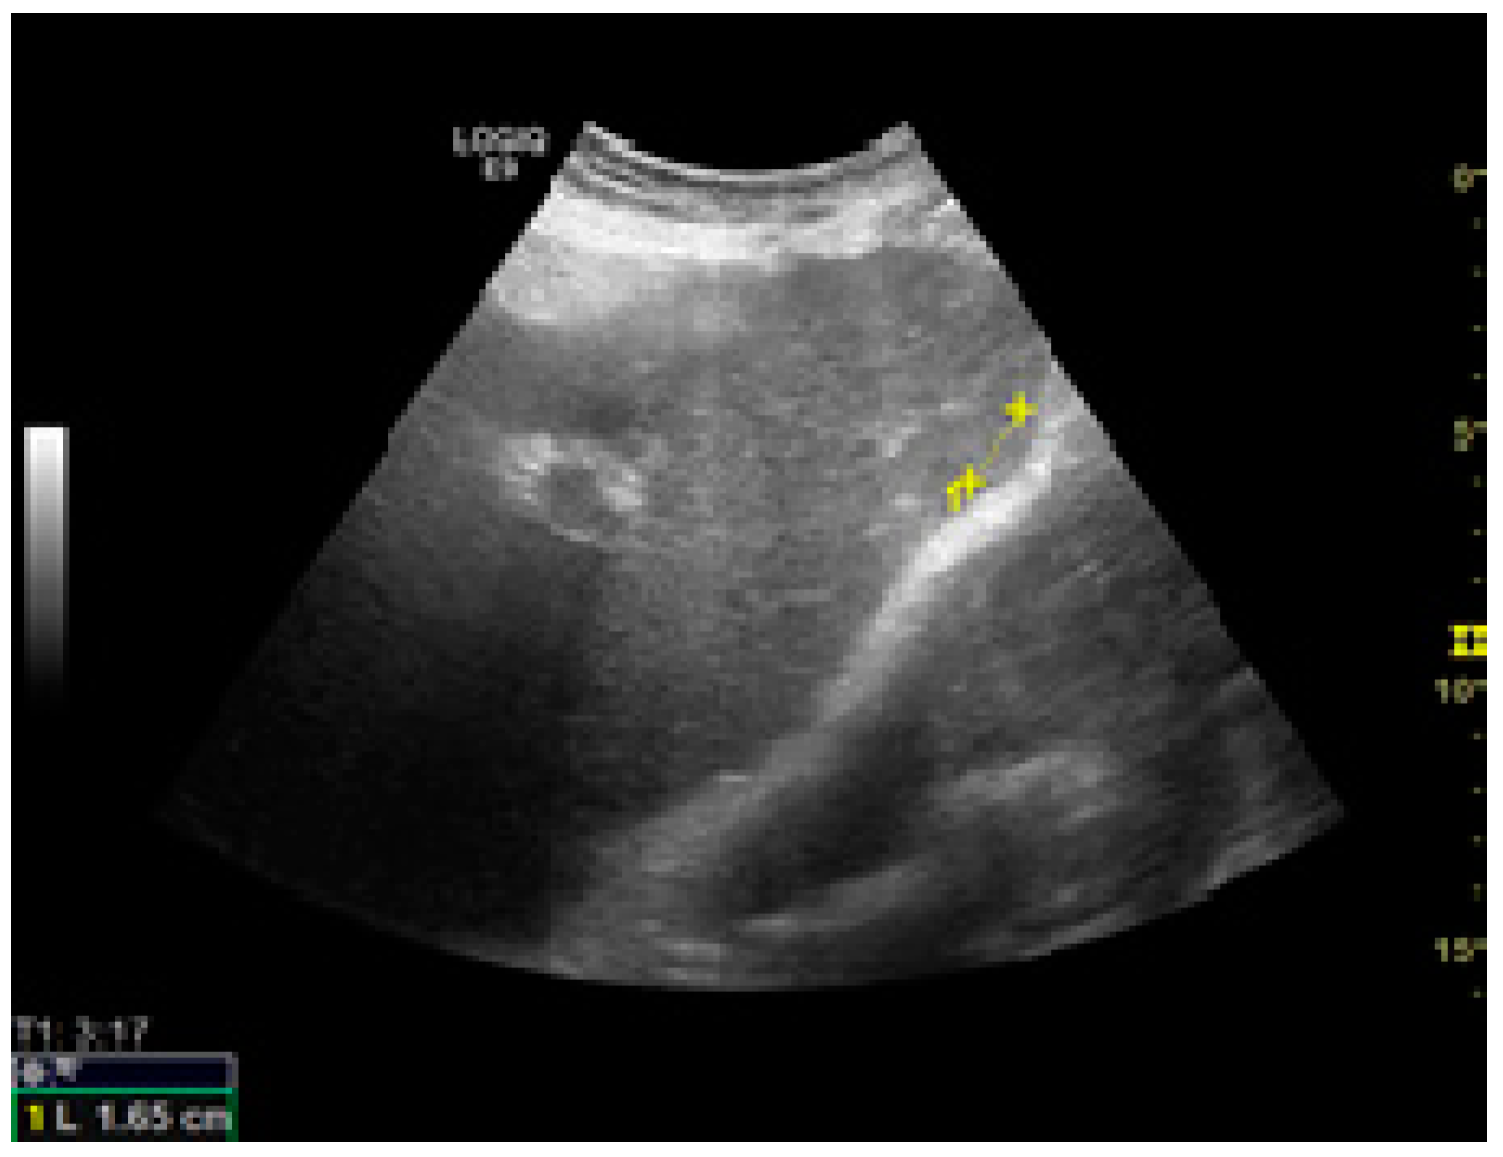

| Key Morphological Feature | Standard Image |

| Vasculature |

|

| |

| Right liver lobe |